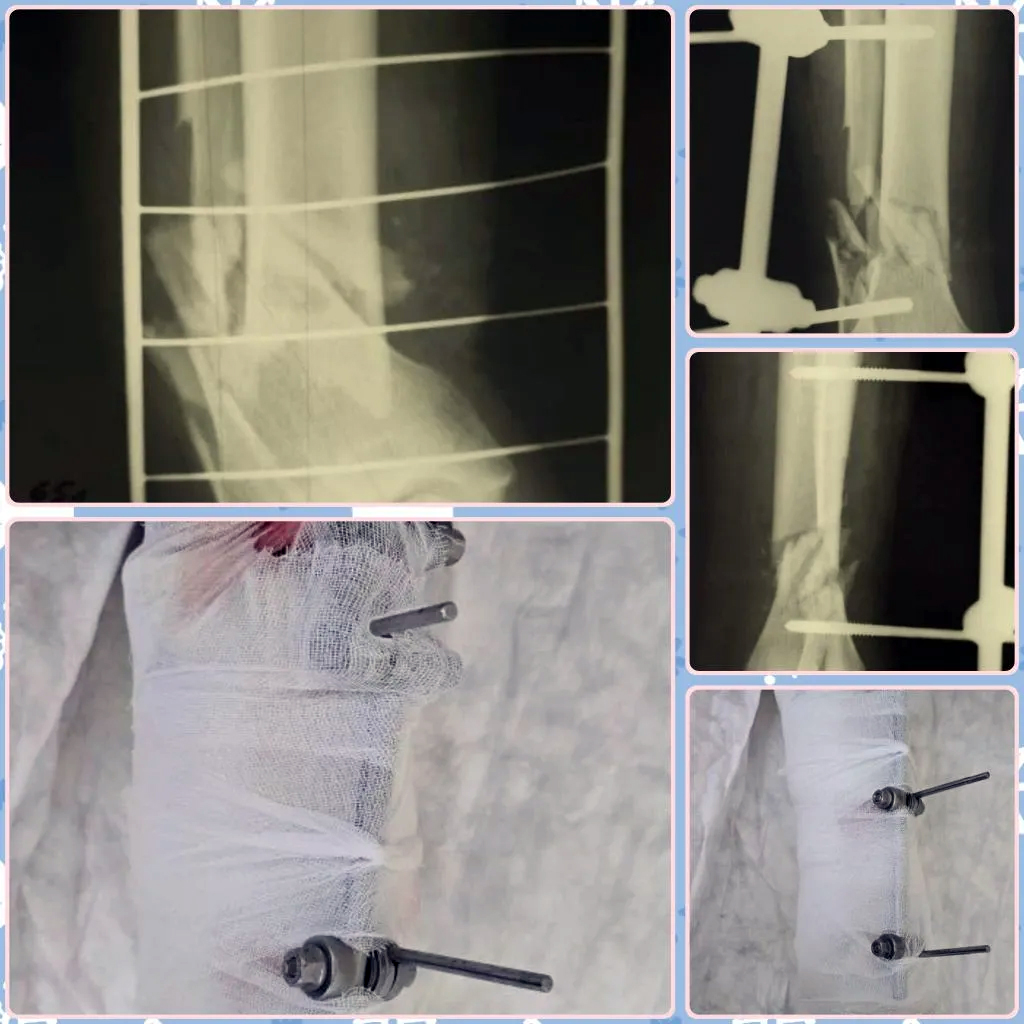

Бытовая цена неосторожности

65-летний мужчина решил помыть окна и упал со стремянки. Итог – тяжелый открытый многооскольчатый перелом обеих костей голени со смещением и обширной рваной раной. Врачам пришлось собирать ногу по кусочкам, стабилизируя кости аппаратом внешней фиксации. Теперь пациента ждет этапное лечение и полная неподвижность конечности на срок от 6 до 8 месяцев. Обычная уборка обернулась длительной инвалидностью.